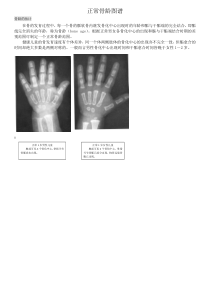

骨龄之对照标准